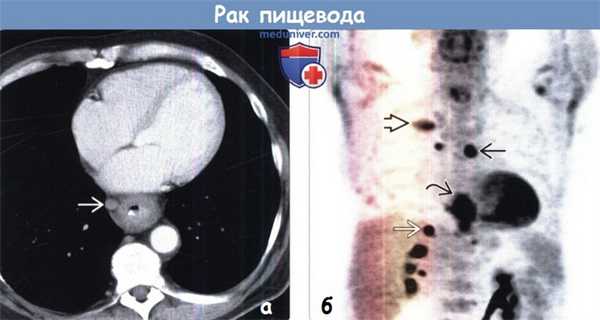

(Слева) На аксиальных ПЭТ/КТ срезах визуализируется очаг гиперфиксации ФДГ, соответствующий первичному раку пищевода.

(Справа) На более каудальных срезах у этого же пациента обнаружен очаг гиперфиксации ФДГ в аортокавальном лимфатическом узле. Кроме того, выявлен очаг накопления ФДГ в объемном образовании левой почки, что свидетельствует о первичном почечноклеточном раке. ПЭТ/КТ самый эффективный метод оценки распространенности поражения, влияющий на принятие итогового решения.

(а) У пациента с аденокарциномой пищевода при КТ с контрастным усилением определяются циркулярное утолщение стенок дистальных отделов пищевода и увеличенный правый параэзофагеальный лимфатический узел.

(б) У этого же пациента при ФДГ-ПЭТ в коронарной плоскости визуализируется интенсивное поглощение ФДГ первичной опухолью, которую сложно отличить от прилежащего параэзофагеального лимфатического узла. Следует отметить наличие лимфаденопатии правой паратрахеальной области и метастазов в заднем отрезке ребра справа и в правом надпочечнике.